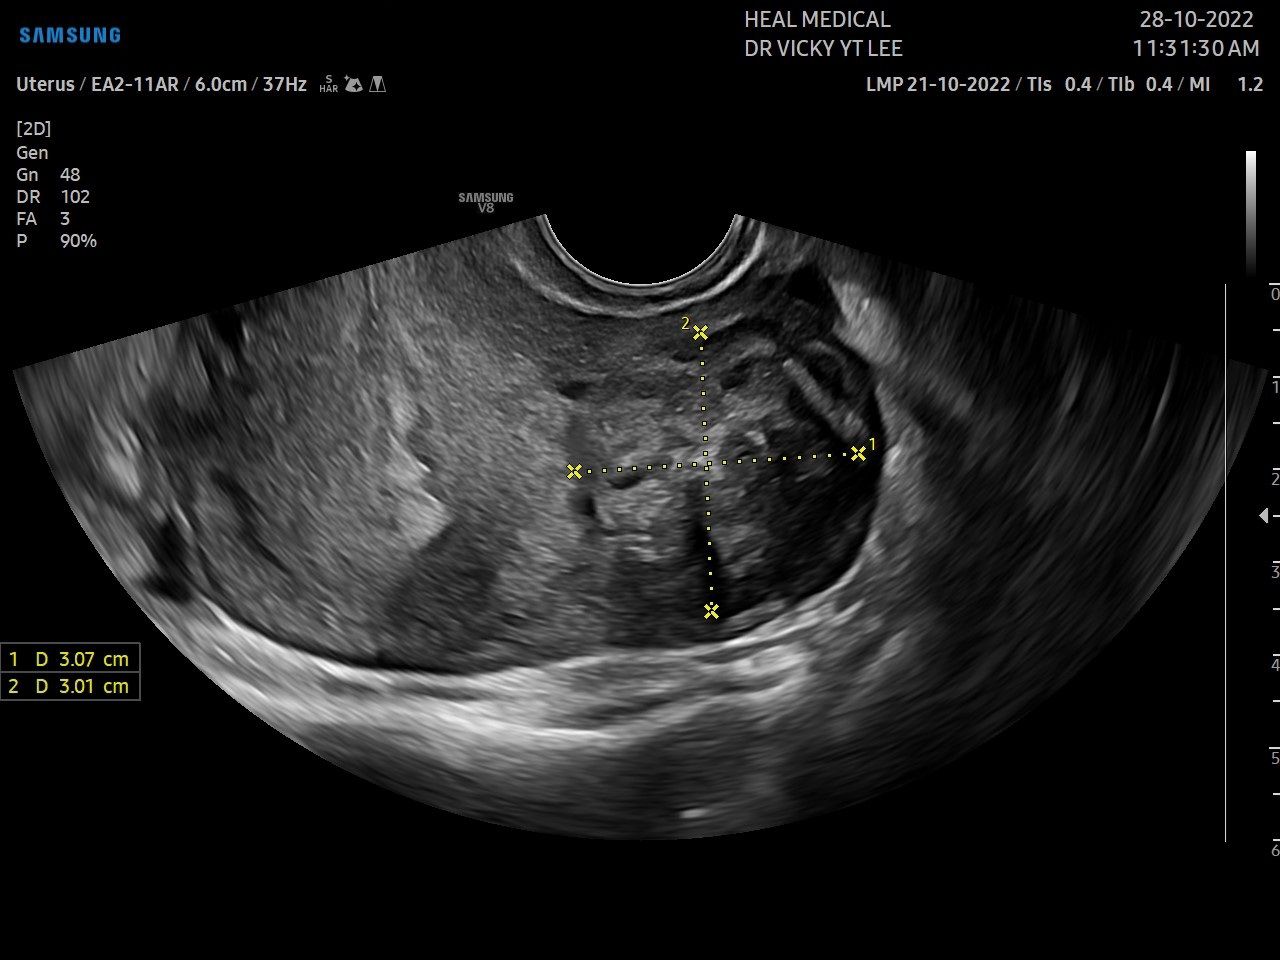

2.JPG

想了解是否患有子宮肌瘤,要透過(guò)婦產(chǎn)科腹部或經(jīng)陰道的超聲波檢查,確認(rèn)肌瘤的大小和位置。

過(guò)半數(shù)患者會(huì)出現(xiàn)月經(jīng)量增加的癥狀,甚至血流不止、月經(jīng)日數(shù)增長(zhǎng)、嚴(yán)重經(jīng)痛等,可能引致貧血,出現(xiàn)頭暈、氣喘、心跳加速、長(zhǎng)期疲倦等問(wèn)題,有什麼方法可以紓緩不適?李醫(yī)生表示首先要進(jìn)行檢查:「透過(guò)超聲波檢查,分析子宮圖像,確認(rèn)肌瘤的大小和位置,如經(jīng)期不定時(shí)、經(jīng)量過(guò)多,需要再做宮腔鏡檢查,以排除因子宮內(nèi)膜病變而引起的問(wèn)題。子宮內(nèi)膜病變會(huì)增生成惡性腫瘤,而患上子宮內(nèi)膜癌。宮腔鏡檢查是內(nèi)窺鏡的一種,經(jīng)陰道放入子宮內(nèi)作檢查,提取內(nèi)膜組織進(jìn)行化驗(yàn),以確認(rèn)有沒(méi)有病變。一般來(lái)說(shuō)肌瘤是不必割除的,透過(guò)藥物治療可減少經(jīng)量及經(jīng)痛,待收經(jīng)後肌瘤有可能會(huì)慢慢縮小。若經(jīng)血過(guò)多、經(jīng)痛嚴(yán)重而藥物無(wú)法控制、肌瘤增大又或者影響生育,則可能需要做手術(shù)。如在宮腔內(nèi)的肌瘤而引致月經(jīng)問(wèn)題,可透過(guò)宮腔鏡切除。如肌瘤在肌肉層要透過(guò)微創(chuàng)或開(kāi)肚手術(shù)切除肌瘤。割除肌瘤有復(fù)發(fā)的可能,如果患者已沒(méi)有繼續(xù)生育的打算,則可以割除整個(gè)子宮,以杜絕復(fù)發(fā)的機(jī)會(huì)。」